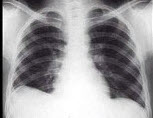

55、单项选择题

男,5岁,高热、畏寒、咳嗽、胸痛1周,如图所示,最可能的诊断为()